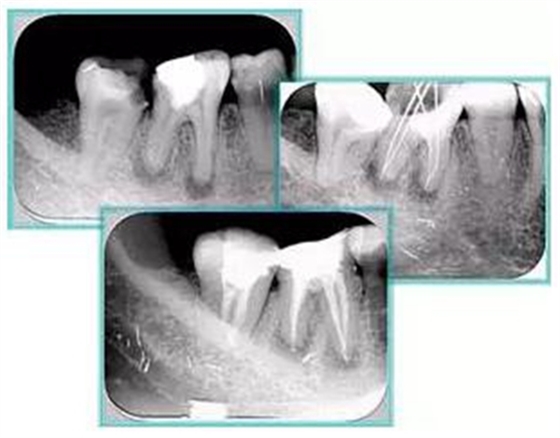

常見(jiàn)有修復(fù)性鈣化和增齡性鈣化。下面為根管鈣化 X 線(xiàn)片。

下圖為器械折斷的 X 線(xiàn)片。箭頭處示折斷器械。

下圖箭頭處示臺(tái)階形成。